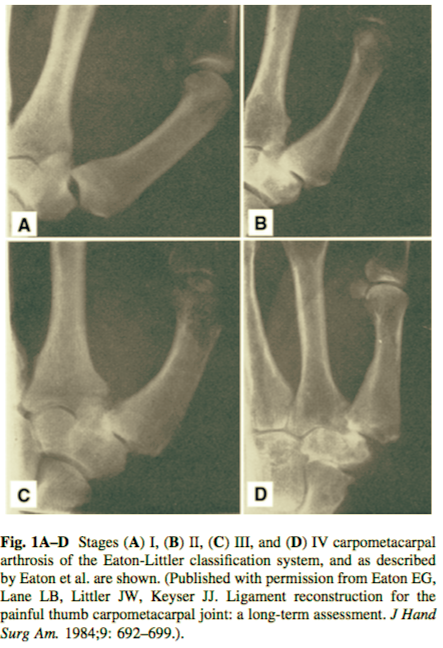

Eaton and Littler Classification of Basilar Thumb Arthritis

Stage I: Subtle carpometacarpal joint space widening.

Stage II: Slight carpometacarpal joint space narrowing, sclerosis, and cystic changes with osteophytes or loose bodies < 2 mm.

Stage III: Advanced carpometacarpal joint space narrowing, sclerosis, and cystic changes with osteophytes or loose bodies > 2 mm.

Stage IV: Arthritic changes in the carpometacarpal joint as in Stage III with scaphotrapezial arthritis.